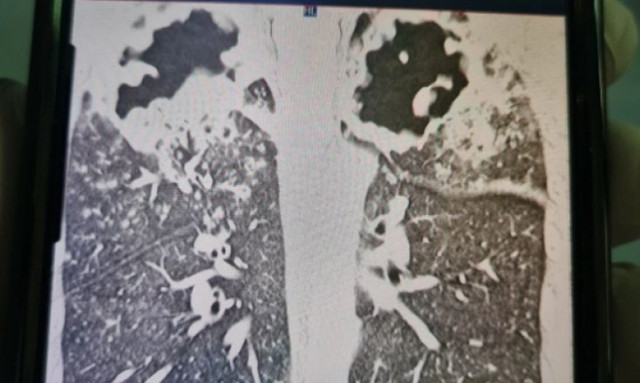

Ένα απερίσκεπτο λάθος έχει φέρει σε εξαιρετικά δύσκολη κατάσταση έναν 33χρονο στην Αυστραλία, καθώς δίνει μάχη για να παραμείνει στη ζωή.

O Chris Capper επισκεπτόταν συχνά τον φίλο του Mount Elliot στο βόρειο Queensland, ωστόσο έκανε το σφάλμα να πει αφιλτράριστο νερό από μια πηγή της περιοχής. Κάτι που του προκάλεσε μια σοβαρή αδιαθεσία.